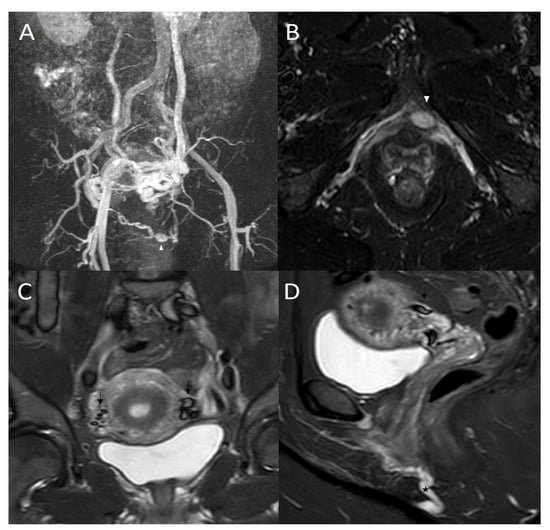

3.2. STIR and Phlebographic Findings